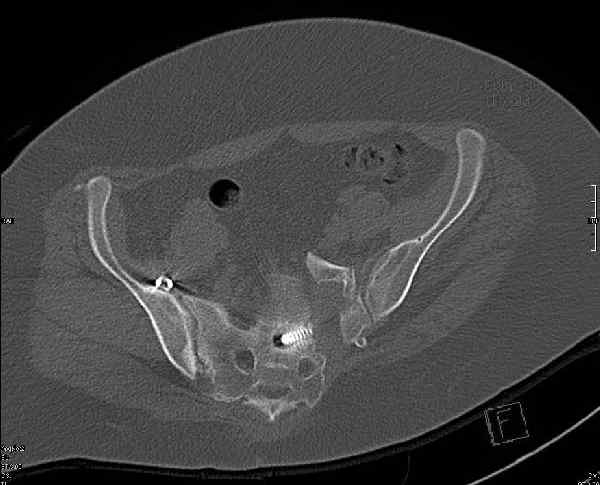

Молодая девушка 19 лет, травма 1 год назад, тогда же прооперирована.

В настоящее время имеются ноющие боли в области крестца слева, нарушение походки, ощущение неуверенности, слабости в левой нижней конечности, неврологически -непостоянные парестезии в левой нижней конечности. Ходит с дополнительной опорой, страдает от ожирения.

В приложении снимки при поступлении и послеоперационные год назад.

Могу сказать одно: миграция винтов и нестабильность синтеза левого подвздошно-крестцовогоо сочленения очевидна.

Мы имели ввиду перелом крестца